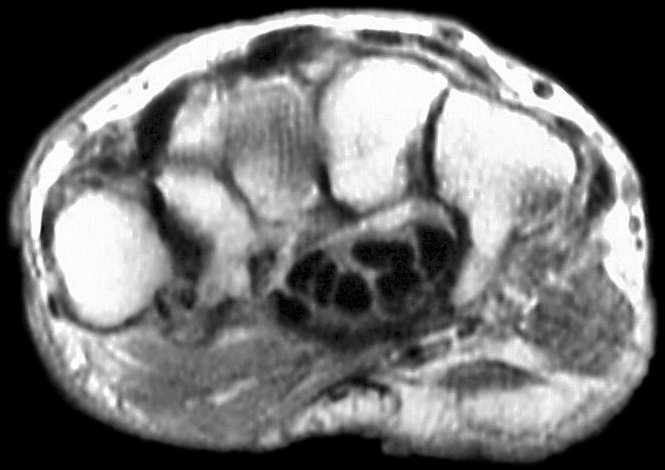

Sections through the carpal tunnel -  looking for a hook of hamate fracture or tendon discontinuity - were read as normal, although there may be a subtle signal irregularity through the hook of the hamate:

Is that a tendon rupture adjacent to the pisotriquetral joint?